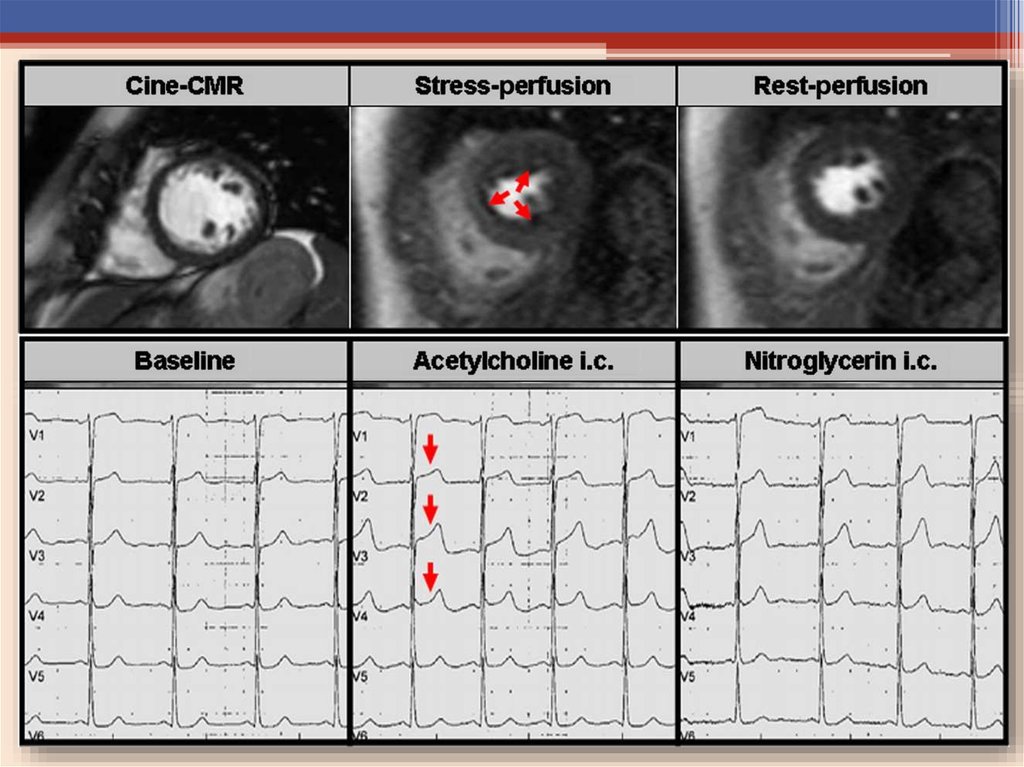

Провокационные пробы

«Золотым стандартом» диагностики Вазоспастической стенокардии

являются интракоронарные провокационные пробы с

• Эргометрином*

• Эргоновином**

• Ацетилхолином***

• А также пробы с гипервентиляцией, холодовые пробы и тесты с